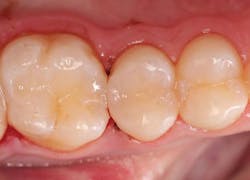

A 19-year-old female presented with a class II lesion on tooth no. 4. After local anesthesia, a conservative slot preparation was accomplished using a #330 pear-shaped carbide, and the remaining caries was removed with a slow-speed round bur (figure 3). A 1–1.5 mm enamel bevel was placed at a 45-degree angle on the occlusal and proximal margins with the very fine flame-shaped diamond (45u) to enhance the enamel etch and marginal seal. The preparation was isolated with a ring-based sectional matrix system (Palodent Plus, Dentsply/Sirona). A selective-etch technique of the enamel margins was employed, and the universal bonding agent was applied according to the DFU. Then, it was light cured for 20 seconds. Omnichroma was placed in two separate increments in the class II preparation, and then condensed and shaped with composite instruments. Each layer was exposed to the LED curing light for 20 seconds from the buccal, lingual, and finally, occlusal. After removal of the ring, wedge, and sectional matrix, the occlusion was checked in the usual manner, and shaping and polishing were completed using the same carbide burs and abrasive cup/point system as the class V restoration in case no. 1 (figure 4).Case no. 3